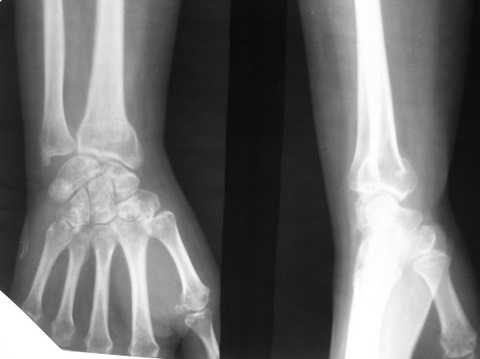

на Ргр нарастают явления остеопороза, не смотря на прием препаратов кальция.

В гипсовом повязке наблюдалось вторичное смещение костных отломков по длине (при передне-заднем рентгенограмме), и при боковй проекции видно смещение отломка в дорсальном направлении и таким

образом последный дает компрессию нервов в лучезапястном канале (типа синд. Зудека)

Этого синдрома купировать почти невозможно на долгий срок, потому что идет постоянная компрессия в канале. остеопопроз это из-за нарушения

иннерваций область кисти.

Это так называемый"синдром Зудека",дистрофия Зудека,пятнистый остеопороз Зудека .Амбулаторные травматологи на повторном

приеме довольно часто встречаются с данной патологией.Интересно то,что начинаются проблемы после снятия гипса.Часто лечение

занимает больше времени,чем обычный перелом "луча" в разы.В основе лежат сосудистые и нейротрофические расстройства.